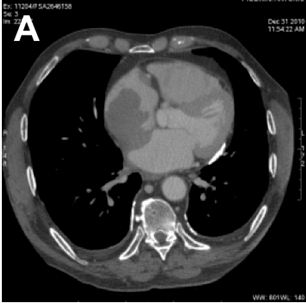

Recurrence of Testicular Large B-Cell Non-Hodgkin’s Lymphoma Presenting as Right Atrium Mass: A Case Report